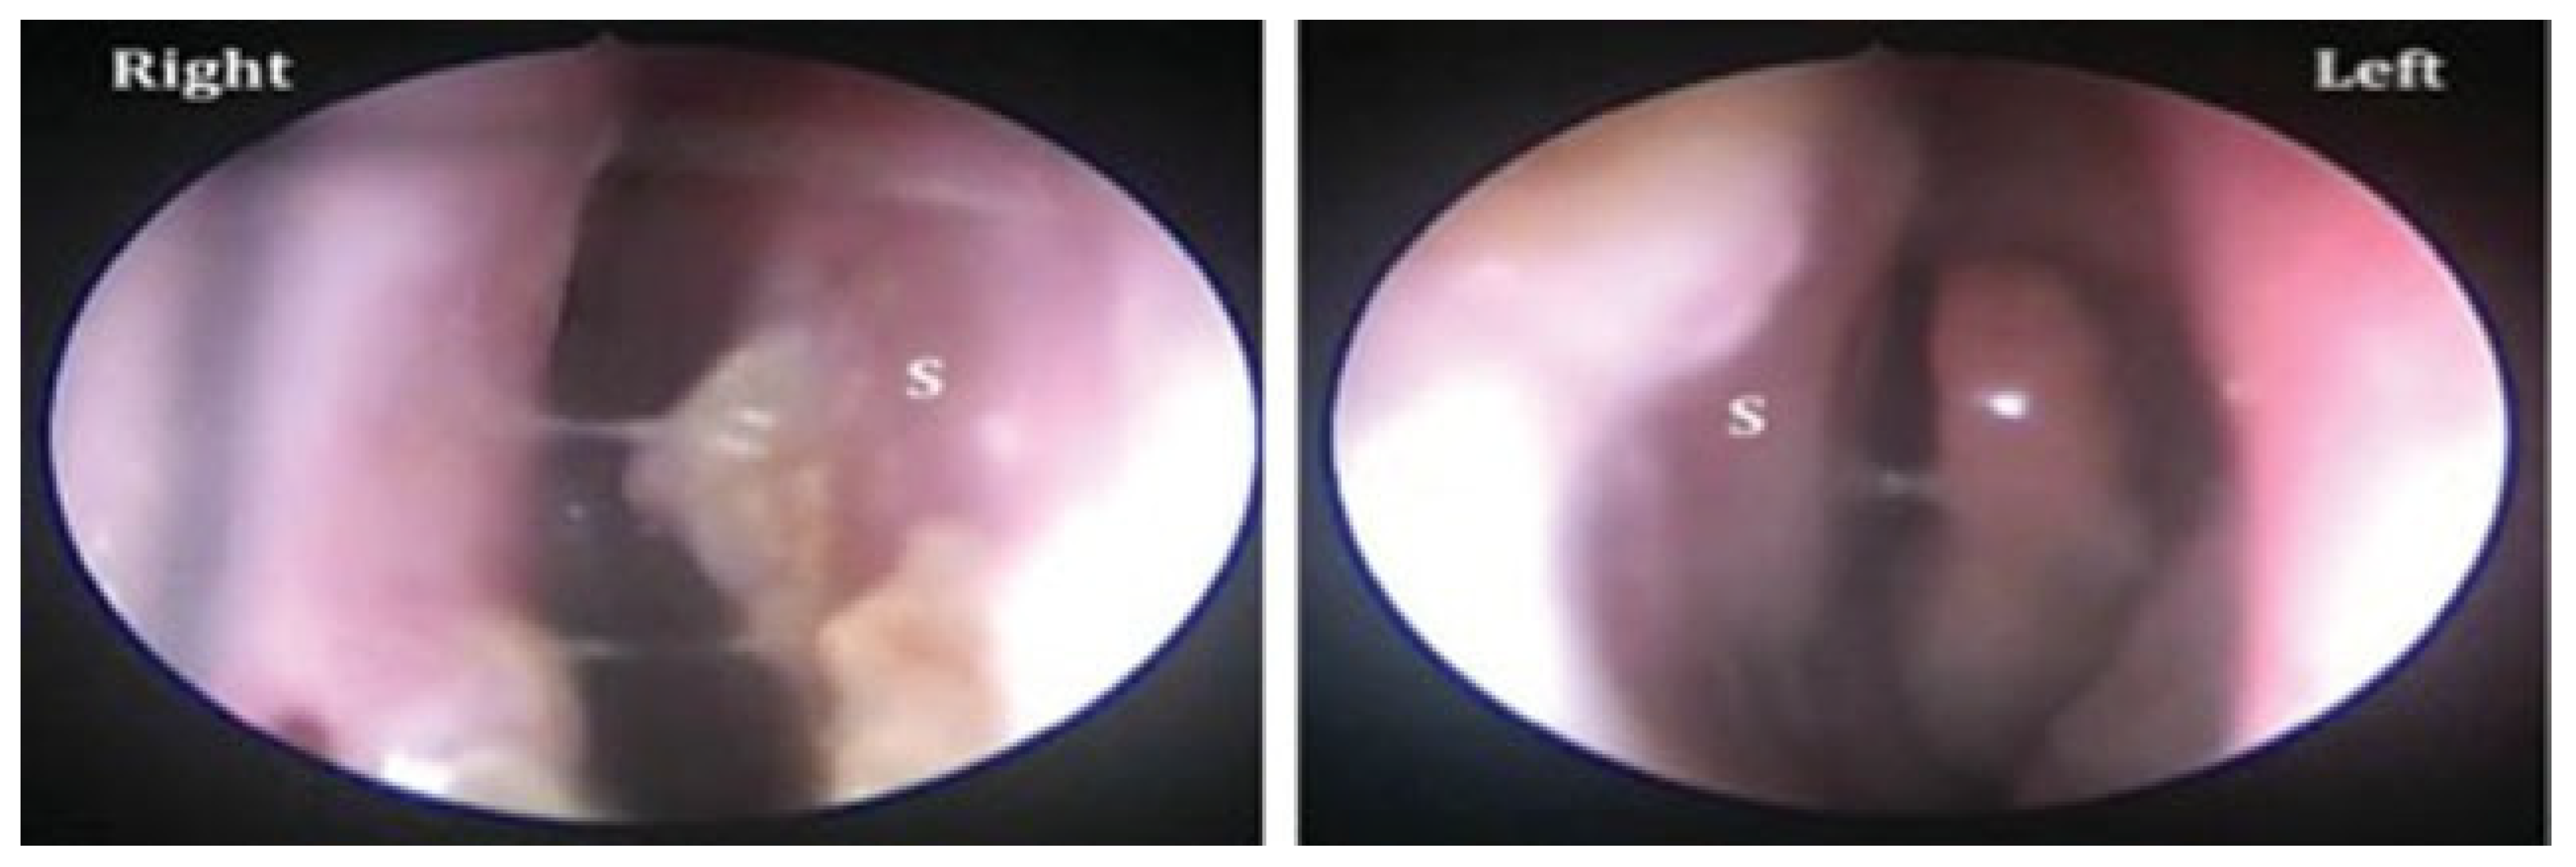

Figure 2. Endoscopic view of the healed perforation from right and left nasal cavities at the 3-week postoperative visit. The septum (S) is shown with minimum crusting and complete closure of the perforation.

On examination, the perforation was noted to be anterior in location, measuring 1.7 cm × 1.7 cm (Figure 1). The patient was taken to the operating room and a septal perforation repair was performed using a combination of a standard external rhinoplasty approach and a tunneled pericranial flap harvested through a coronal incision (see section “Surgical Technique” for details). Intraoperatively, the viability of the pericranial flap was confirmed using intraoperative laser angiography using the SPY system. The patient was admitted for pain control and wound management. He was discharged on postoperative day 5. Intranasal Silastic splints were left in place for 21 days postoperatively. Nasal endoscopy performed at 3 months follow-up demonstrated complete closure of perforation with mild mucosal crusting (Figure 1). Follow up at 1, 3, and 10 weeks confirmed a stable repair with well-healed mucosa and no evidence of recurrent perforation. Follow up at 5 years revealed a completely healed repair.